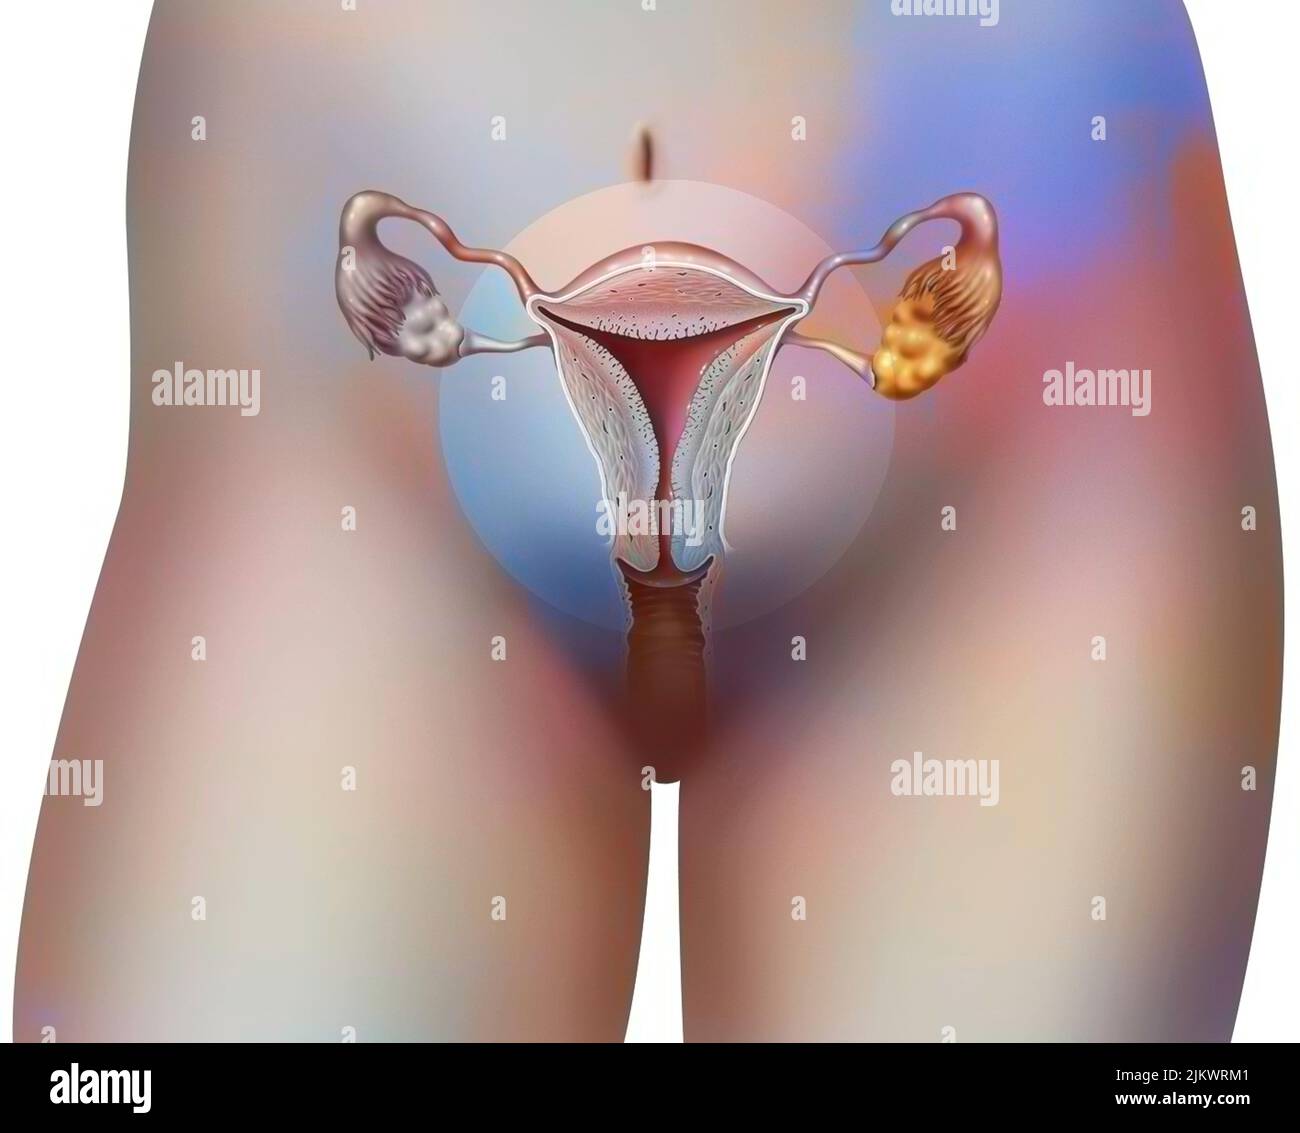

RF2JKWRM1–Vue antérieure des organes génitaux féminins avec vagin, utérus, trompes de Fallope, ovaires.